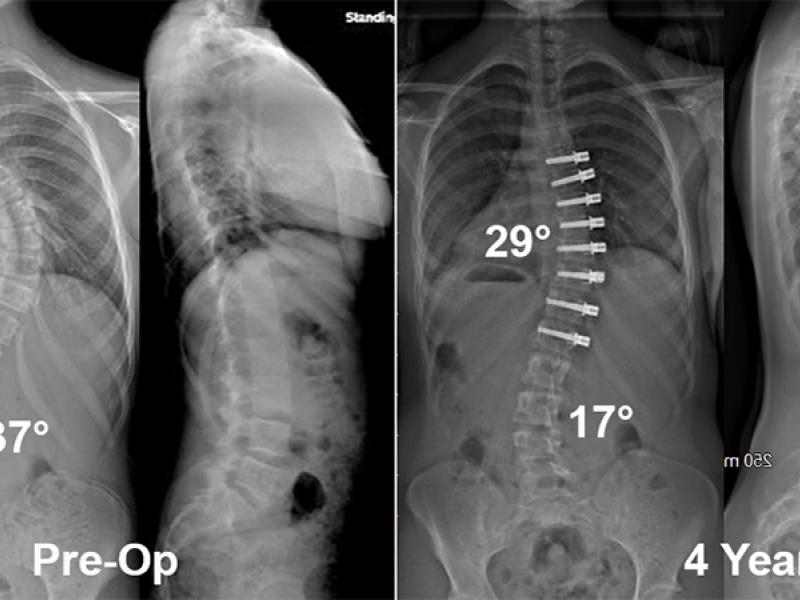

The Journal of Bone and Joint Surgery recently published a study led by Dr. Daniel